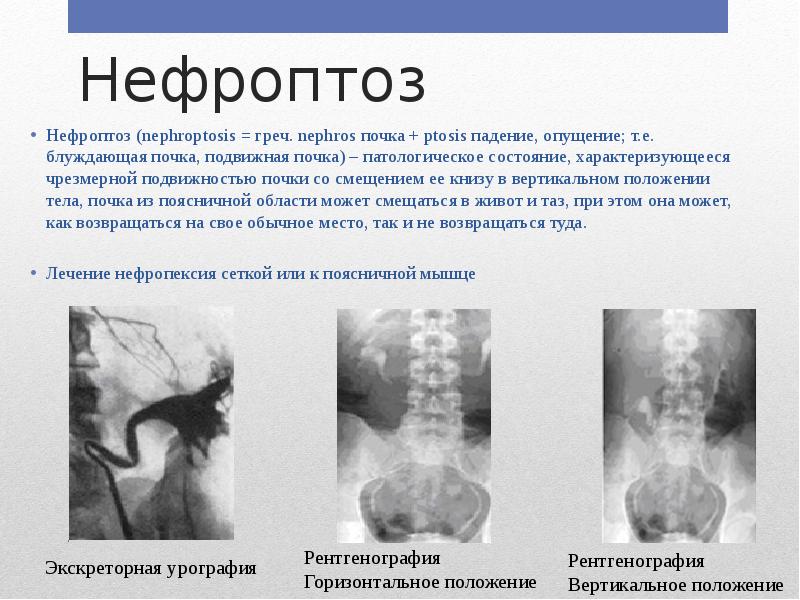

Экскреторная урография при нефроптозе: диагностические изображения

.png)

Раздел: Кладезь мудрости